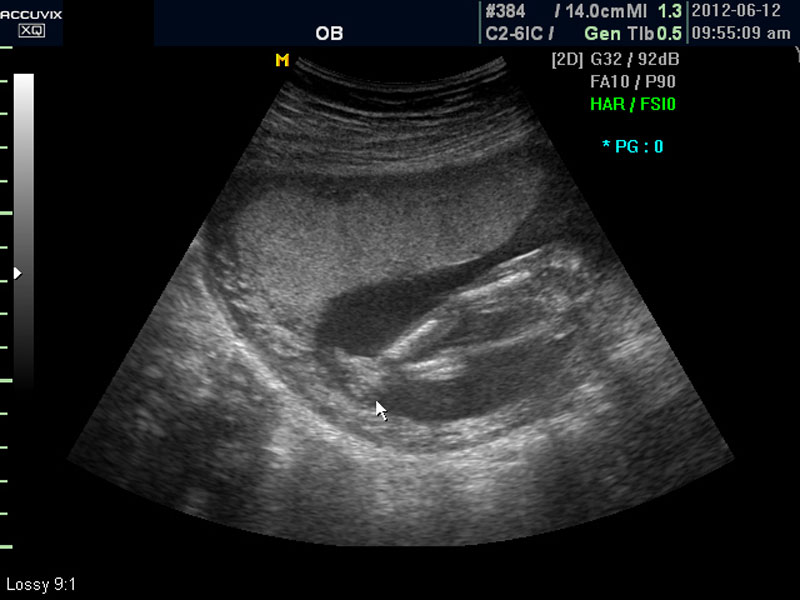

태아에 대한 관찰이 끝나면 태반의 위치와 양수의 양을 살펴 보는데 아직 태반의 위치는 고정된 것이 아니라 크게 의미는 없지만 이때부터의 위치는 대체로 임신 후반까지 크게 바뀌는 것은 아니며 또한 완전 전치 태반과 같은 경우는 임신 중기부터 출혈등의 증상이 나타날 수 있어 관찰이 필요한 대상입니다.

화면에서는 위쪽에 하얗게 균일하게 보이는 것이 태반의 모습입니다.

태반은 실제로 보면 피자처럼 둥그런 원판 모양이며 임신 후기로 갈수록 태아와 마찬가지로 크기가 커지고 두꺼워집니다.

모든 사진에서 우측 하단에는 기본적인 발육 정보가 기록되는데 세번째 사진에서 빨간 펜으로 표시한 부분이며 그 내용의 의미는 아래와 같습니다.

참고로 이런 측정 수치가 나타나는 양식이나 위치는 초음파 장비마다 다르지만 용어는 대체로 공통된 의학 용어를 사용하기 때문에 대동소이합니다.